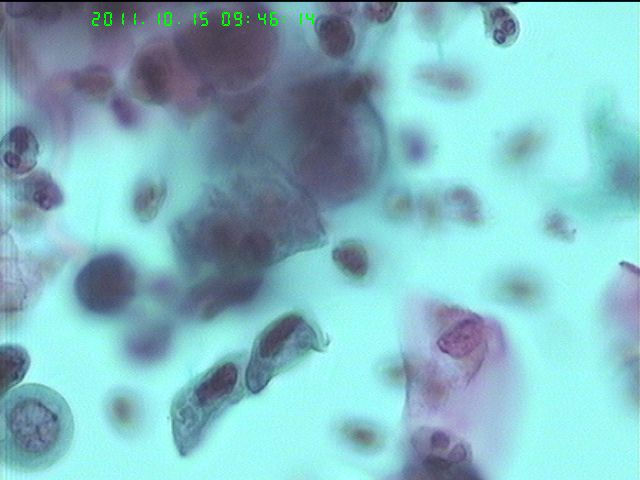

28岁,LCT

• LCT等你判读图1

图1

活检:CIN2-3

呵呵,活检结果 符合细胞学